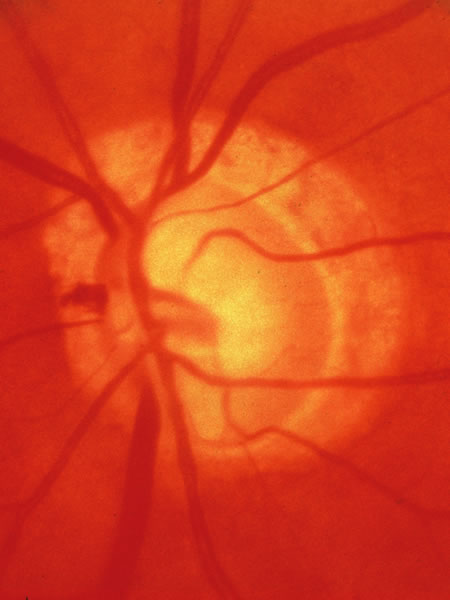

Fig. 34. Photograph of a normal left eye at a time when the right eye had an attack of anterior ischemic optic neuropathy.

Fig. 35. Same eye as Figure 34 during a subsequent attack of ischemic optic neuropathy.

Fig. 36. Same eye as in Figure 34 one year later, with atrophy but no excavation.